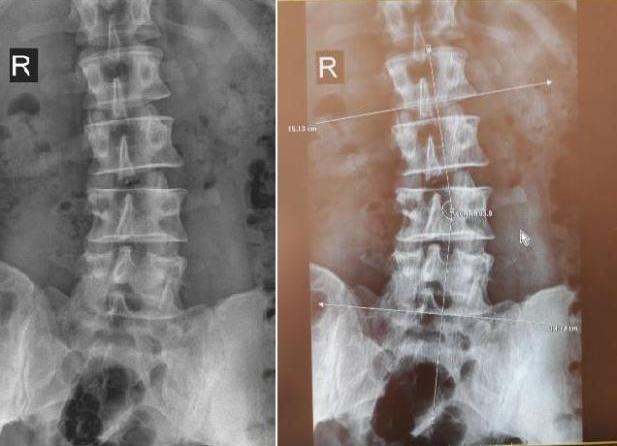

На спондилограммах пояснично-крестцового отдела физиологический лордоз сглажен, продольная ось умеренно отклонена влево, с формированием сколиотической дуги, имеющей вершину в проекции тела L3 позвонка и угол искривления до 17 градусов. Тела позвонков в дугу входящих ротированы - контрлатерально. Правосторонняя клиновидная деформация и снижение высоты межпозвоночных дисков L-2 - L-4 двигательных сегментов. Поперечные отростки тела Th12 удлинены и представлены в виде рудиментарных добавочных ребер. Поперечные отростки L5-позвонка массивные и образуют двусторонний синхондроз c боковыми массами крестца. Незаращение задней дужки S1-позвонка (spina bifida posterior). Заострены передние углы тел позвонков. Субхондральный склероз замыкательных пластинок тел позвонков на протяжении.

Заключение: Рентгенологическая картина остеохондроза пояснично-крестцового отдела позвоночника 2-й степени, с нарушением статики - левосторонним сколиозом 2-й степени по Коббу, на фоне лестничной деформации спинномозгового канала. Врожденная аномалия L5 — полная сакрализация позвонка. Spina bifida posterior S1.